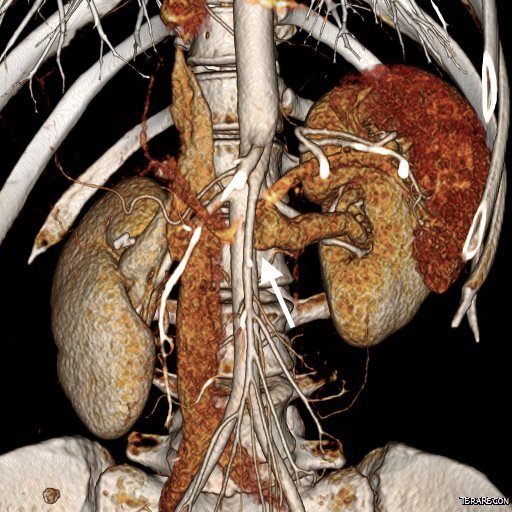

On examination, she was tender over the left kidney and flank. Laboratory examination was positive for microscopic hematuria. CT venography (below) showed an obstruction of her left renal vein by the superior mesenteric artery. Drainage via gonadal vein was not demonstrated, and no pelvic varices or complex of retroperitoneal veins was apparent.

00084038664_20170420_1.jpg

pre and post ctv comparison.png

Left renal vein at widest is 22mm, with expansion, possibly up to 28mm, but is relatively short. Do you see the SMA?